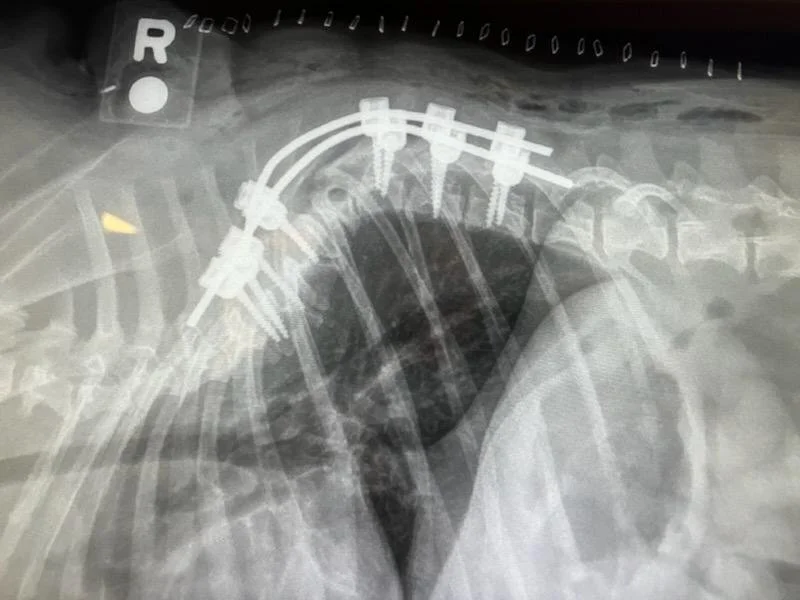

5 kg Pug subtotal corpectomy with stabilization

7 kg French Bulldog dorsal laminectomy with stabilization

8 kg Shih Tzu, C5 - C7 stabilization

8 kg French Bulldog, dorsal laminectomy and stabilization